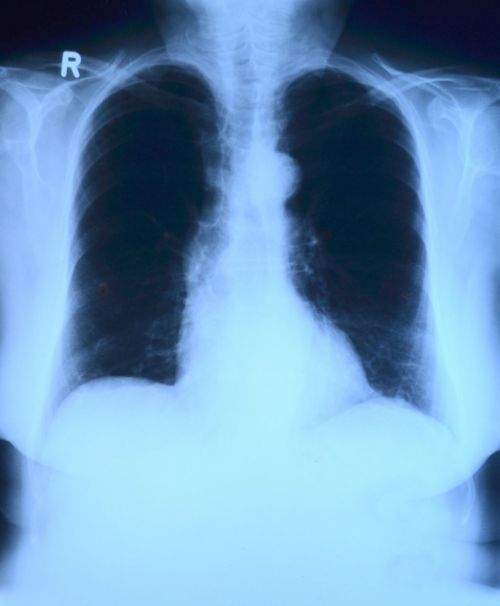

Боль в реберной клетке, которая начинается после травмы, обычно диагностируется с помощью рентгеновского снимка для выявления переломов костей и повреждений. МРТ и другие виды сканирования могут обнаруживать повреждение мягких тканей.

4. Рак

Одним из симптомов рака легких является боль в грудной клетке или в груди, которая усиливается при глубоком дыхании, кашле или смехе. Другие симптомы, которые следует обратить внимание - кашель с кровью или мокротой, одышка и свистящее дыхание.